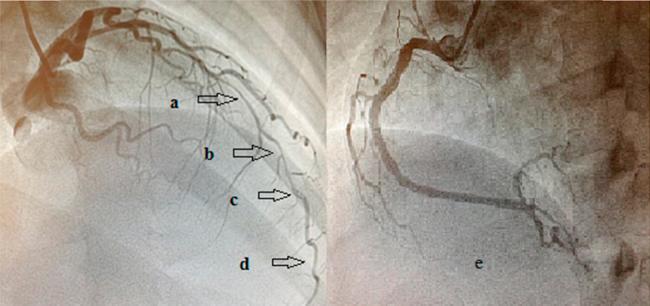

Spontaneous coronary artery dissection (SCAD) is a rare entity. It has been described in various settings like pregnancy, collagen vascular diseases, cocaine abuse, heavy exercise, variant angina, eosinophilic arteritis, or fibro muscular dysplasia. It is also easy to miss a dissection during angiography, as the typical radiolucent lumen seen in coronary angiography may be absent in many cases. In this report, we describe the case of a 35-year-old female who presented with acute ST elevation myocardial infarction due to spontaneous coronary dissection. She had been having episodic chest pain for one year and had been seen by two different cardiologists but was thought to have non-cardiac symptoms. Even during the index hospitalization, she underwent coronary angiography three times before coronary dissection could be identified as the cause of her symptoms. She underwent coronary artery bypass graft surgery uneventfully. However, even after myocardial revascularization, she has had multiple episodes of chest pain requiring hospitalization. However, we have not been able to find a specific cause for it and the cause of her recurrent chest pain remains an enigma. This case highlights the problems, which arise while managing a case of SCAD. More research is needed to find the exact etiology and long-term prognosis of this condition.